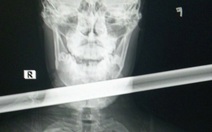

Ngày 10-10, Bệnh viện Đa khoa Xuyên Á Tây Ninh cho biết đã tiếp nhận trường hợp ông L.V.H. (74 tuổi, Tây Ninh) trong tình trạng vết thương hở phức tạp vùng cổ, suy hô hấp cấp.

Người nhà kể lại trong lúc sử dụng máy xịt nước áp lực cao, ông bất cẩn tuột tay, dòng nước mạnh từ vòi xịt đã vô tình cắt sâu vào vùng cổ, kèm theo vết thương hở ở cẳng tay. Rất may, bó mạch máu lớn (động mạch cảnh), thần kinh quan trọng không bị tổn thương.

Ngay khi nhập viện, tình trạng người bệnh nguy kịch, bệnh nhân tổn thương gần như đứt nhóm cơ vùng cổ, rách thanh mạc, tổn thương sụn giáp - sụn nhẫn, khí quản bị cắt ngang. Chỉ cần vết thương lan rộng thêm vài milimet và làm đứt động mạch cảnh hai bên, nguy cơ tử vong nhanh.